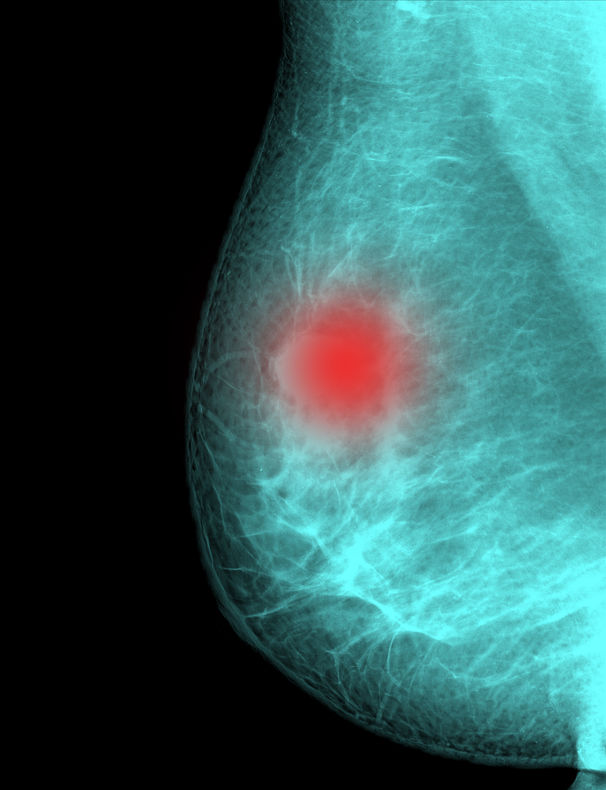

A mammogram is an x-ray that gives a picture of the internal structure of the breast. There are two types of mammography: Screening and Diagnostic. Screening mammography is performed on asymptomatic women to check for undetected tumors. Diagnostic mammography is used to follow up on breast abnormalities detected during a self exam or check-up.

Mammography is the leading defense against breast cancer. MHS offers digital mammograms, a procedure capturing images of the breast image special electronic x-ray detector, which converts the image into a digital picture for review on a computer monitor. With digital mammography, the magnification, orientation, brightness, and contrast of the image may be altered after the exam is completed to help the radiologist more clearly see certain areas.

In standard mammography, images are recorded on film using an x-ray cassette. The film is viewed by the radiologist using a “lightbox” and then stored in a jacket in the facility’s archives. With digital mammography, the breast image is captured using a special electronic x-ray detector, which converts the image into a digital picture for review on a computer monitor. The digital mammogram is then stored on a computer. With digital mammography, the magnification, orientation, brightness, and contrast of the image may be altered after the exam is completed to help the radiologist more clearly see certain areas.

It is suspected that digital mammography is superior in some women because it allows radiologists to heighten the contrast between dense tissue and cancerous cells, which both appear to be white on a film mammogram.